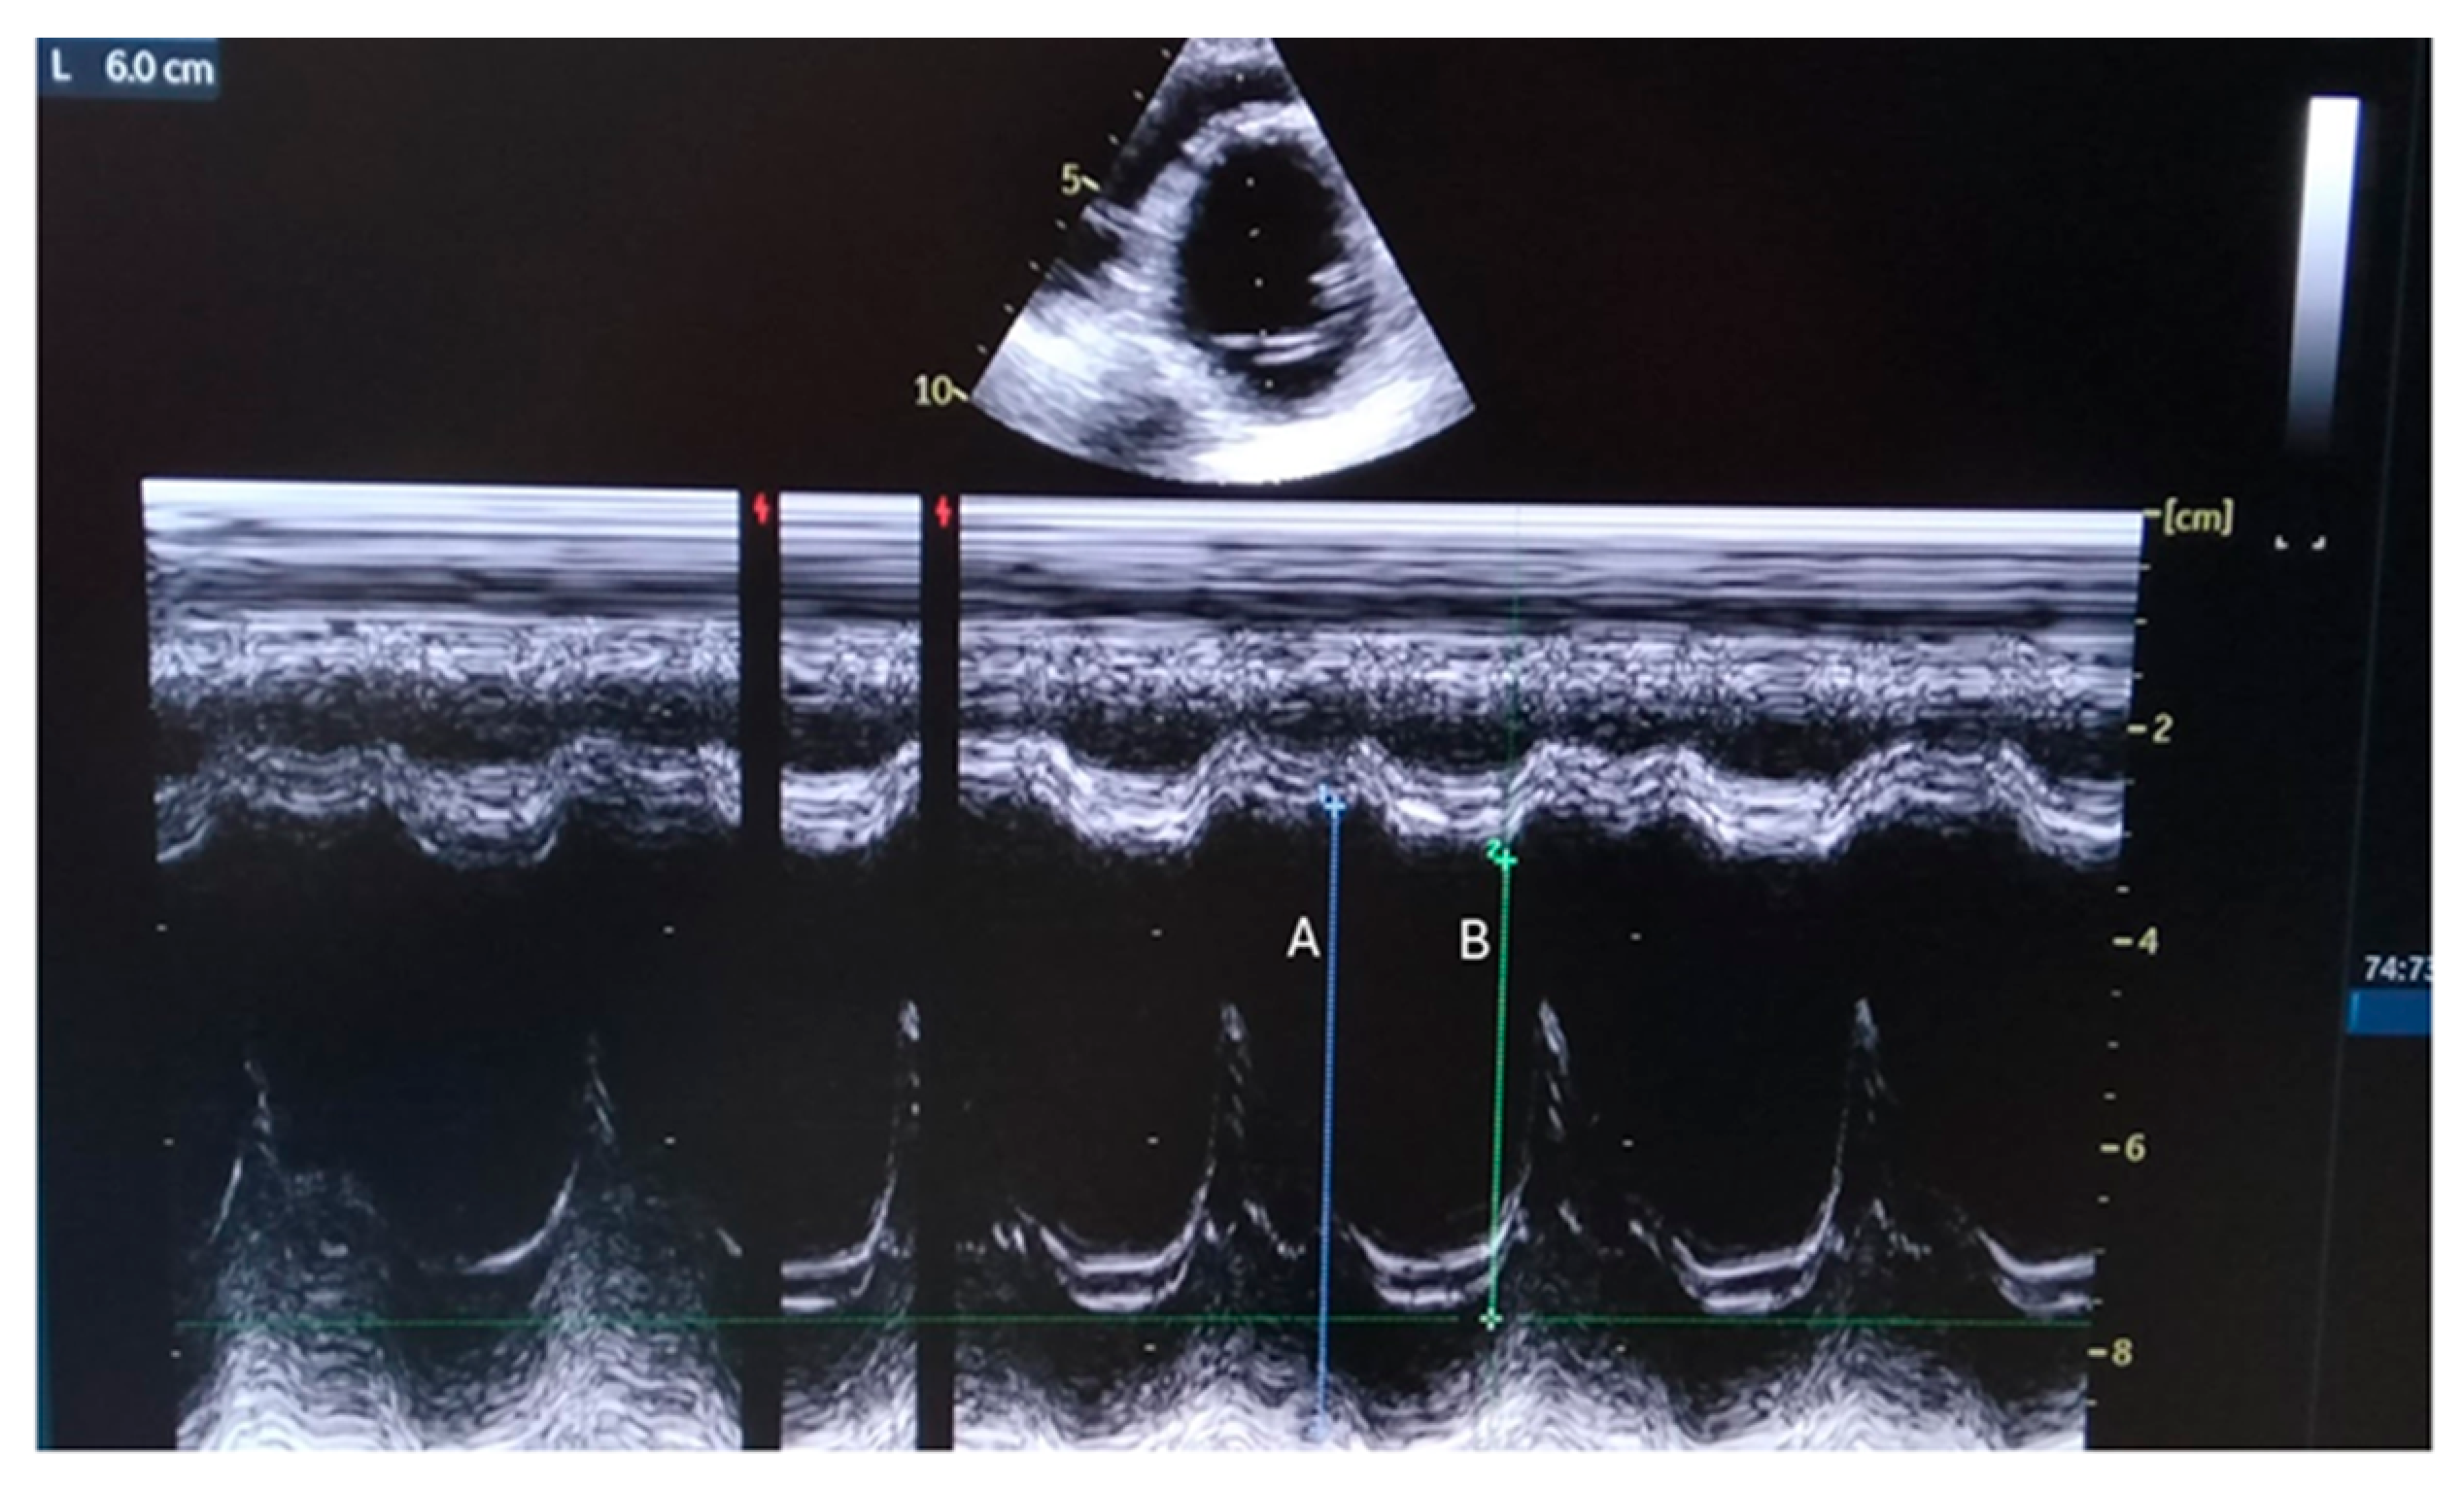

| LVEF (%) | 35–38 |

| LVEF (%) | 20 |

| LVEF at the last observation (%) | Less than 20 |

| LVEF (%) | 50% |

| LVEF (%) | 20% |

| LVEF at the last observation (%) | 33% |